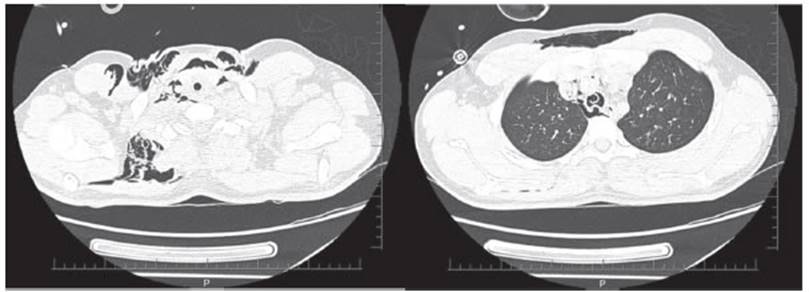

En

UCI evoluciona con broncoespasmo grave, desaturación

hasta el 63 % con dosis crecientes de noradrenalina (de 0,06 μg/kg/min a 0,2 μg/kg/min)

y tendencia a la hipotermia. En los exámenes de control, se

detectó acidosis láctica (10,2 mMol/L)

con pH 7,17 y HCO3 de

18 mEq/L. Al tercer día, se palparon

crepitaciones cervicales y el escáner de tórax reveló

enfisema subcutáneo cervical y neuÂmotórax (Figura 1), por lo que

se instaló un tubo pleural y se modificó la programación

ventilatoria. Se incluyeron bolos de metilprednisolona

(500 mg por tres veces). El VT

se redujo a 3,4 mL/kg de peso corporal

predicho, la FR a 10 rpm, el tiempo inspiÂratorio 0,72 s, la ventilación

minuto (VE) 2,6

L/min y la relación I:E = 1:7, sin PEEP. Con

este patrón, la Pmáx bajó a 48

cmH2O

y la PEEPi alcanzó los 6 cmH2O. Debido a la hipercapnia, se

asoció con ECCO2R

arteriovenoso (Novalung®️).